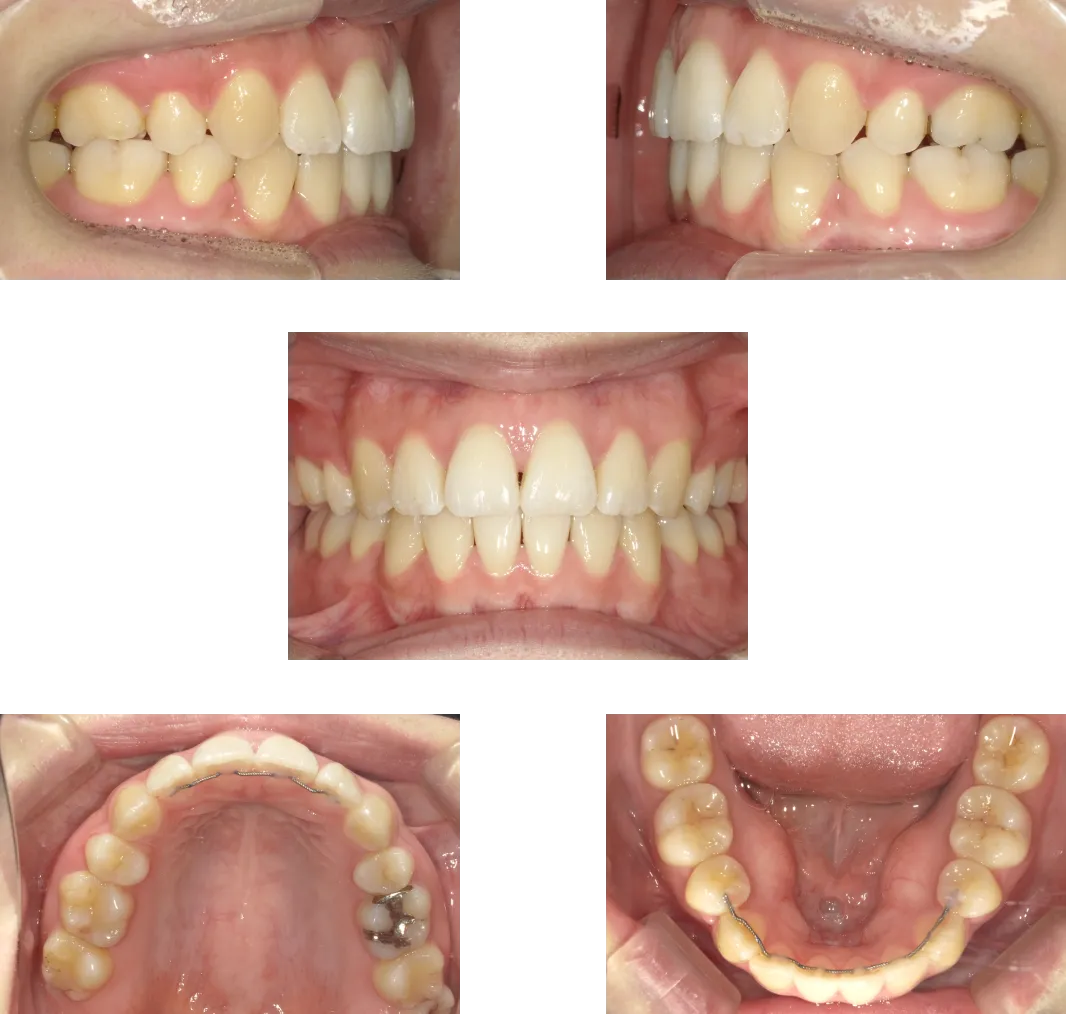

上顎前突 -15歳-

• Before

• After

診断

上顎の前歯唇側傾斜

治療期間

1年6ヶ月+保定期間2年

料金

950,000円

抜歯

なし

リスク

痛み、軽度の歯根吸収、術後の変化